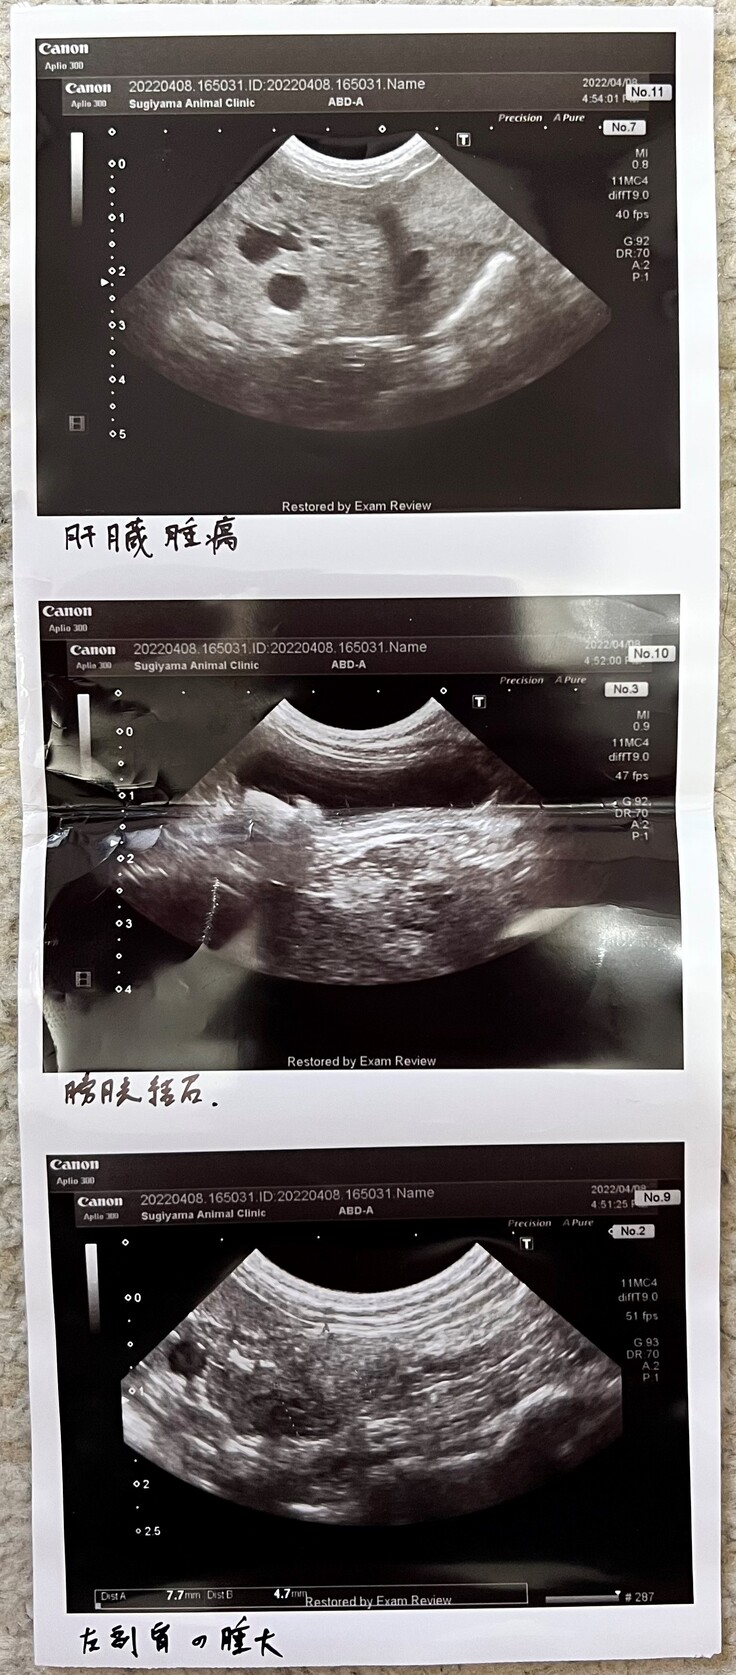

↓掲載許可を得ています

大学病院での血液検査 ALP:通常が89〜の所ポールはなんと3500以上 びっくりです。

岐阜大学動物病院で撮ったCT画像